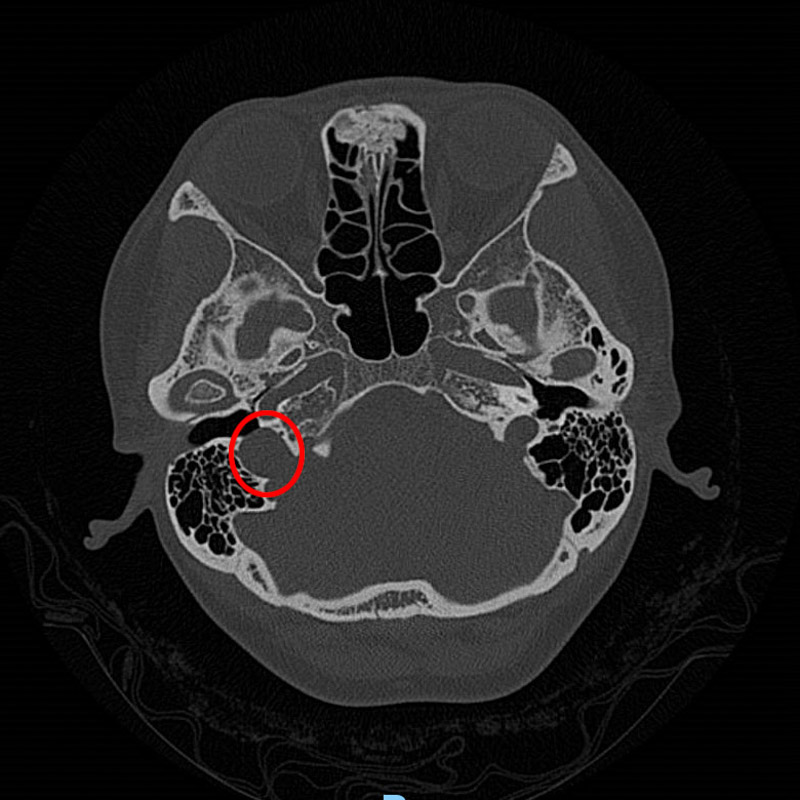

接診醫生了解情況后,為韋女士做了耳內鏡及聽力學檢查,并沒發現異常,但根據患者的實際情況并結合多年的經驗判斷,患者的右耳有可能患有血管搏動性耳鳴。為了進一步證實,患者進行了高分辨頭顱CT檢查,果不其然,放射科醫生在CT影像學中發現了蛛絲馬跡:患者的右側頸靜脈球高位,可疑合并前壁和外側壁缺損。這就是導致韋女士耳鳴的罪魁禍首!